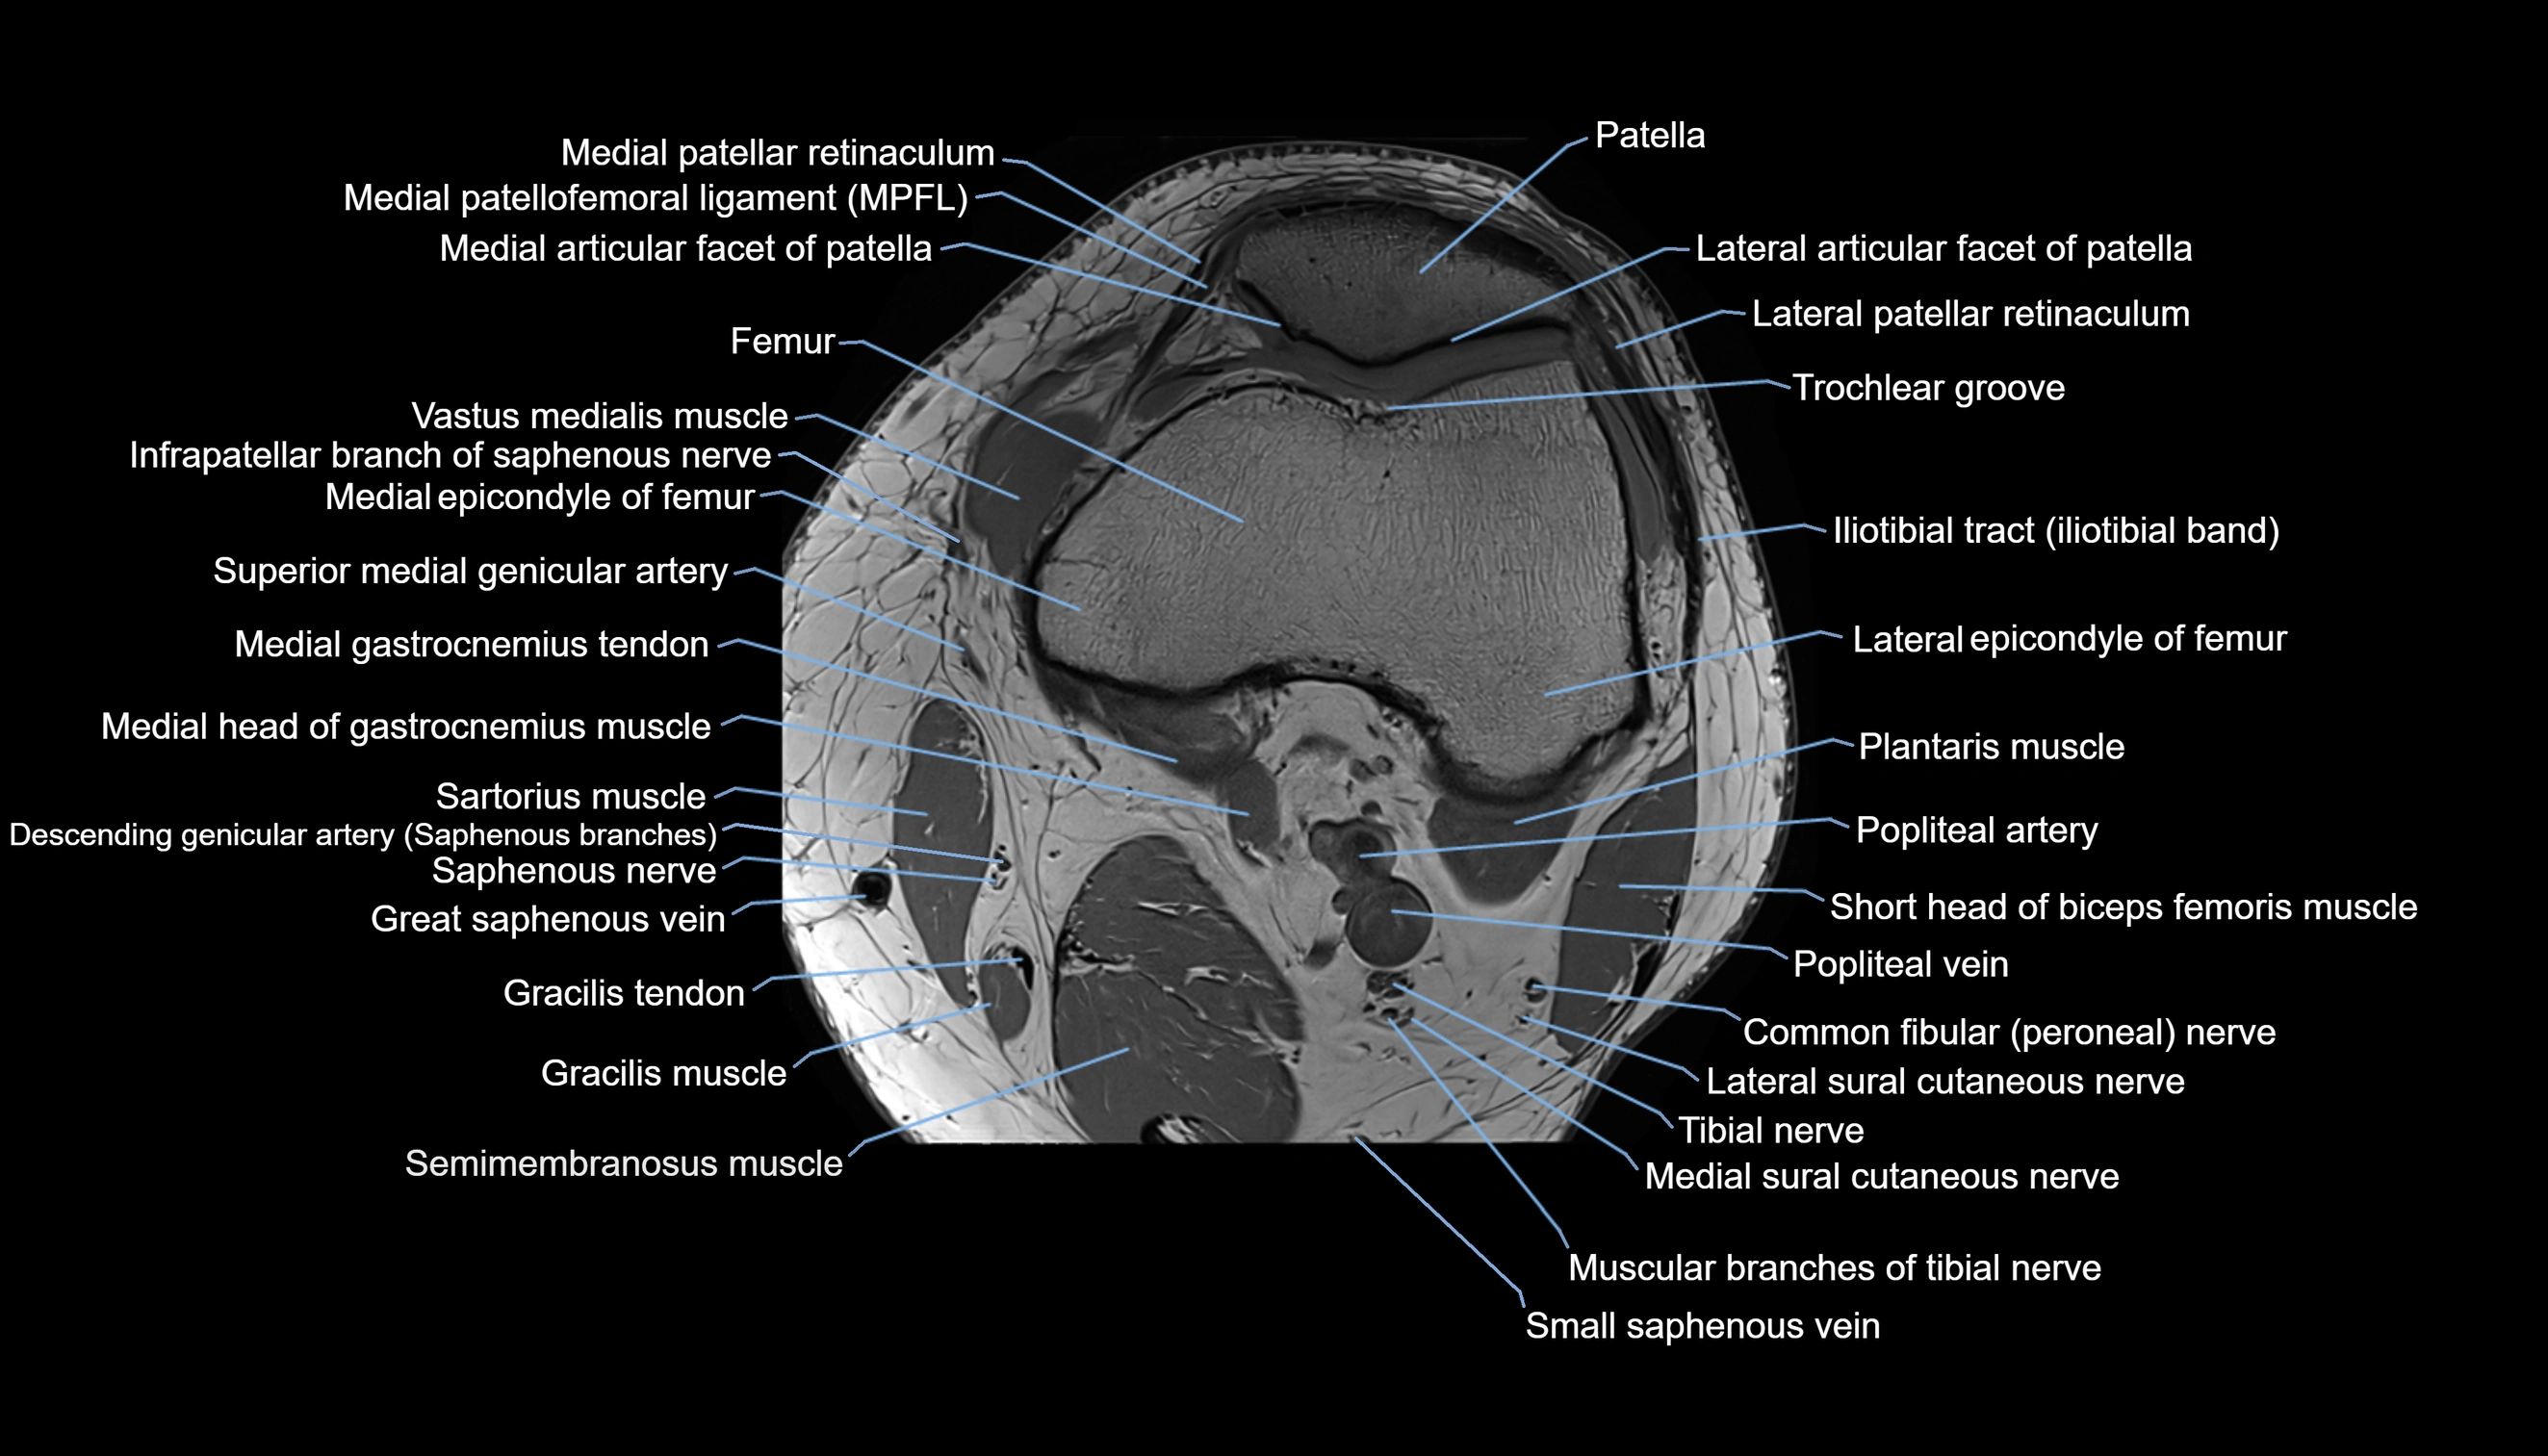

- Femoral condyle articular cartilage

- Infrapatellar branch of saphenous nerve

- Lateral articular facet of patella

- Lateral epicondyle of femur

- Lateral gastrocnemius tendon

- Lateral head of gastrocnemius muscle

- Lateral patellar retinaculum

- Lateral patellofemoral ligament

- Lateral sural cutaneous nerve

- Medial articular facet of patella

- Medial epicondyle of femur

- Medial gastrocnemius tendon

- Medial head of gastrocnemius muscle

- Medial patellar retinaculum

- Medial patellofemoral ligament

- Medial sural cutaneous nerve

- Muscular branches of tibial nerve

- Patella

- Patellar articular cartilage

- Popliteal artery

- Popliteal vein

- Saphenous nerve

- Sartorius muscle

- Semimembranosus muscle

- Small saphenous vein

- Soleus muscle

- Tibial nerve

- Trochlear groove

- great saphenous vein